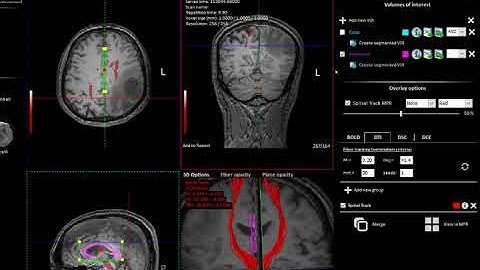

nordicBrainEx v2.1 How to perform dti analysis